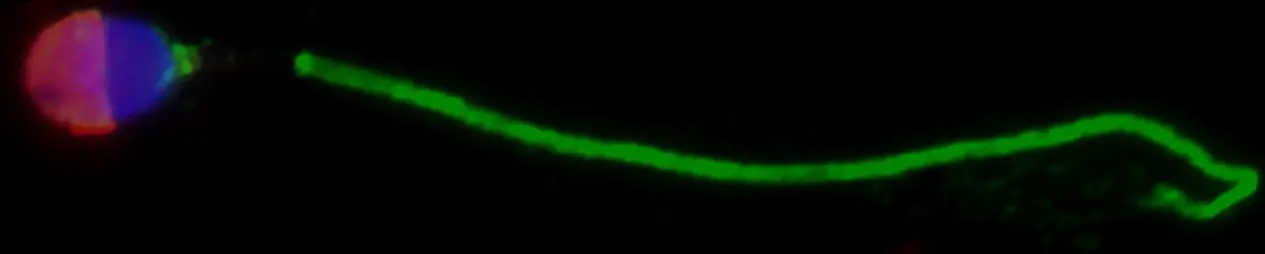

精子细胞和睾丸组织的免疫荧光显微镜;AKAP4(绿色)、ASPX(红色)和细胞核(蓝色)。图片来源:Andrei Drabovich

经过分析,他的团队在患有 NOA 的男性的完整精子中发现了两种蛋白质 AKAP4 和 ASPX。他们使用一种名为成像流式细胞术的方法表明,ASPX 位于精子头部,而 AKAPA4 则位于精子尾部。在成像流式细胞术中,机器会拍摄单个细胞的图像。运行这些样本后,计算算法会帮助研究人员从数百万张细胞碎片和发育不全精子的图像中挖掘出少数完整的精子细胞。